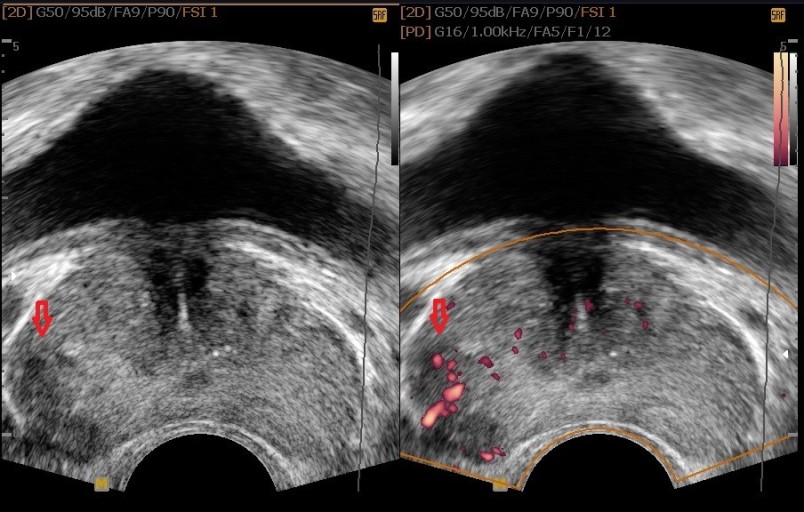

전립선암 초기증상 9. 혈뇨

혈뇨는 소변에 피가 섞여 나오는 증상으로, 상식적으로 신장이나 방광에 문제가 있다는 신호일 수 있으기 때문에 미리 체크를 받아보는 것이 좋아요. 전립선암도 혈뇨의 흔한 원인인데요. 전립선의 암세포는 전립선으로 출혈을 일으켜 혈뇨를 일으킬 수 있지만, 혈뇨는 전립선암의 흔한 증상일 뿐 아니라 요로감염이나 전립선의 거시적 문제와 같은 다른 일시적인 원인으로도 확인될 수 있어요.